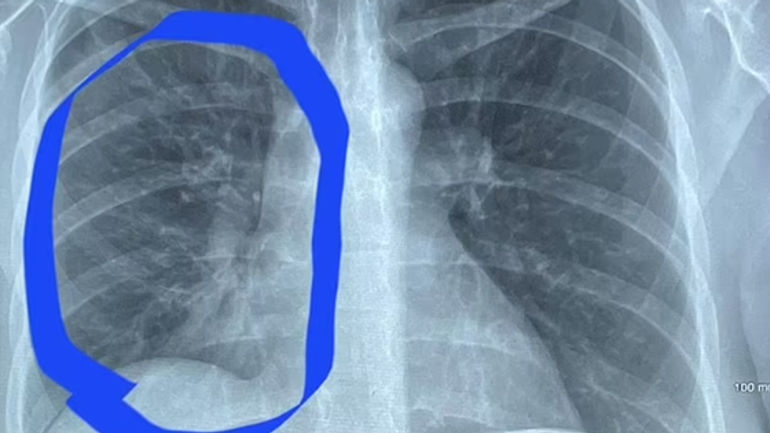

Câu chuyện về Hannah Roth, cô gái 30 tuổi từ Newport, Tennessee, Mỹ, đã gây xôn xao và là bài học đắt giá về hệ quả của thói quen xấu. Roth đối mặt với viêm phổi nặng do hút thuốc lá điện tử, khiến phổi của cô bị tổn thương nặng đến mức bác sĩ so sánh với phổi của một người 80 tuổi. Hành trình chữa trị của Roth là một hành trình đầy thách thức nhưng cũng đầy hy vọng.

Cô gái 30 tuổi có phổi trắng bất thường như cụ già 80

Phổi bị tổn thương nặng nề